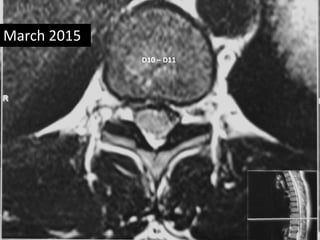

• Follow up MRI was done March 2015

• Complete absorption of fragmant.

March 2015

D10 – D11

D11